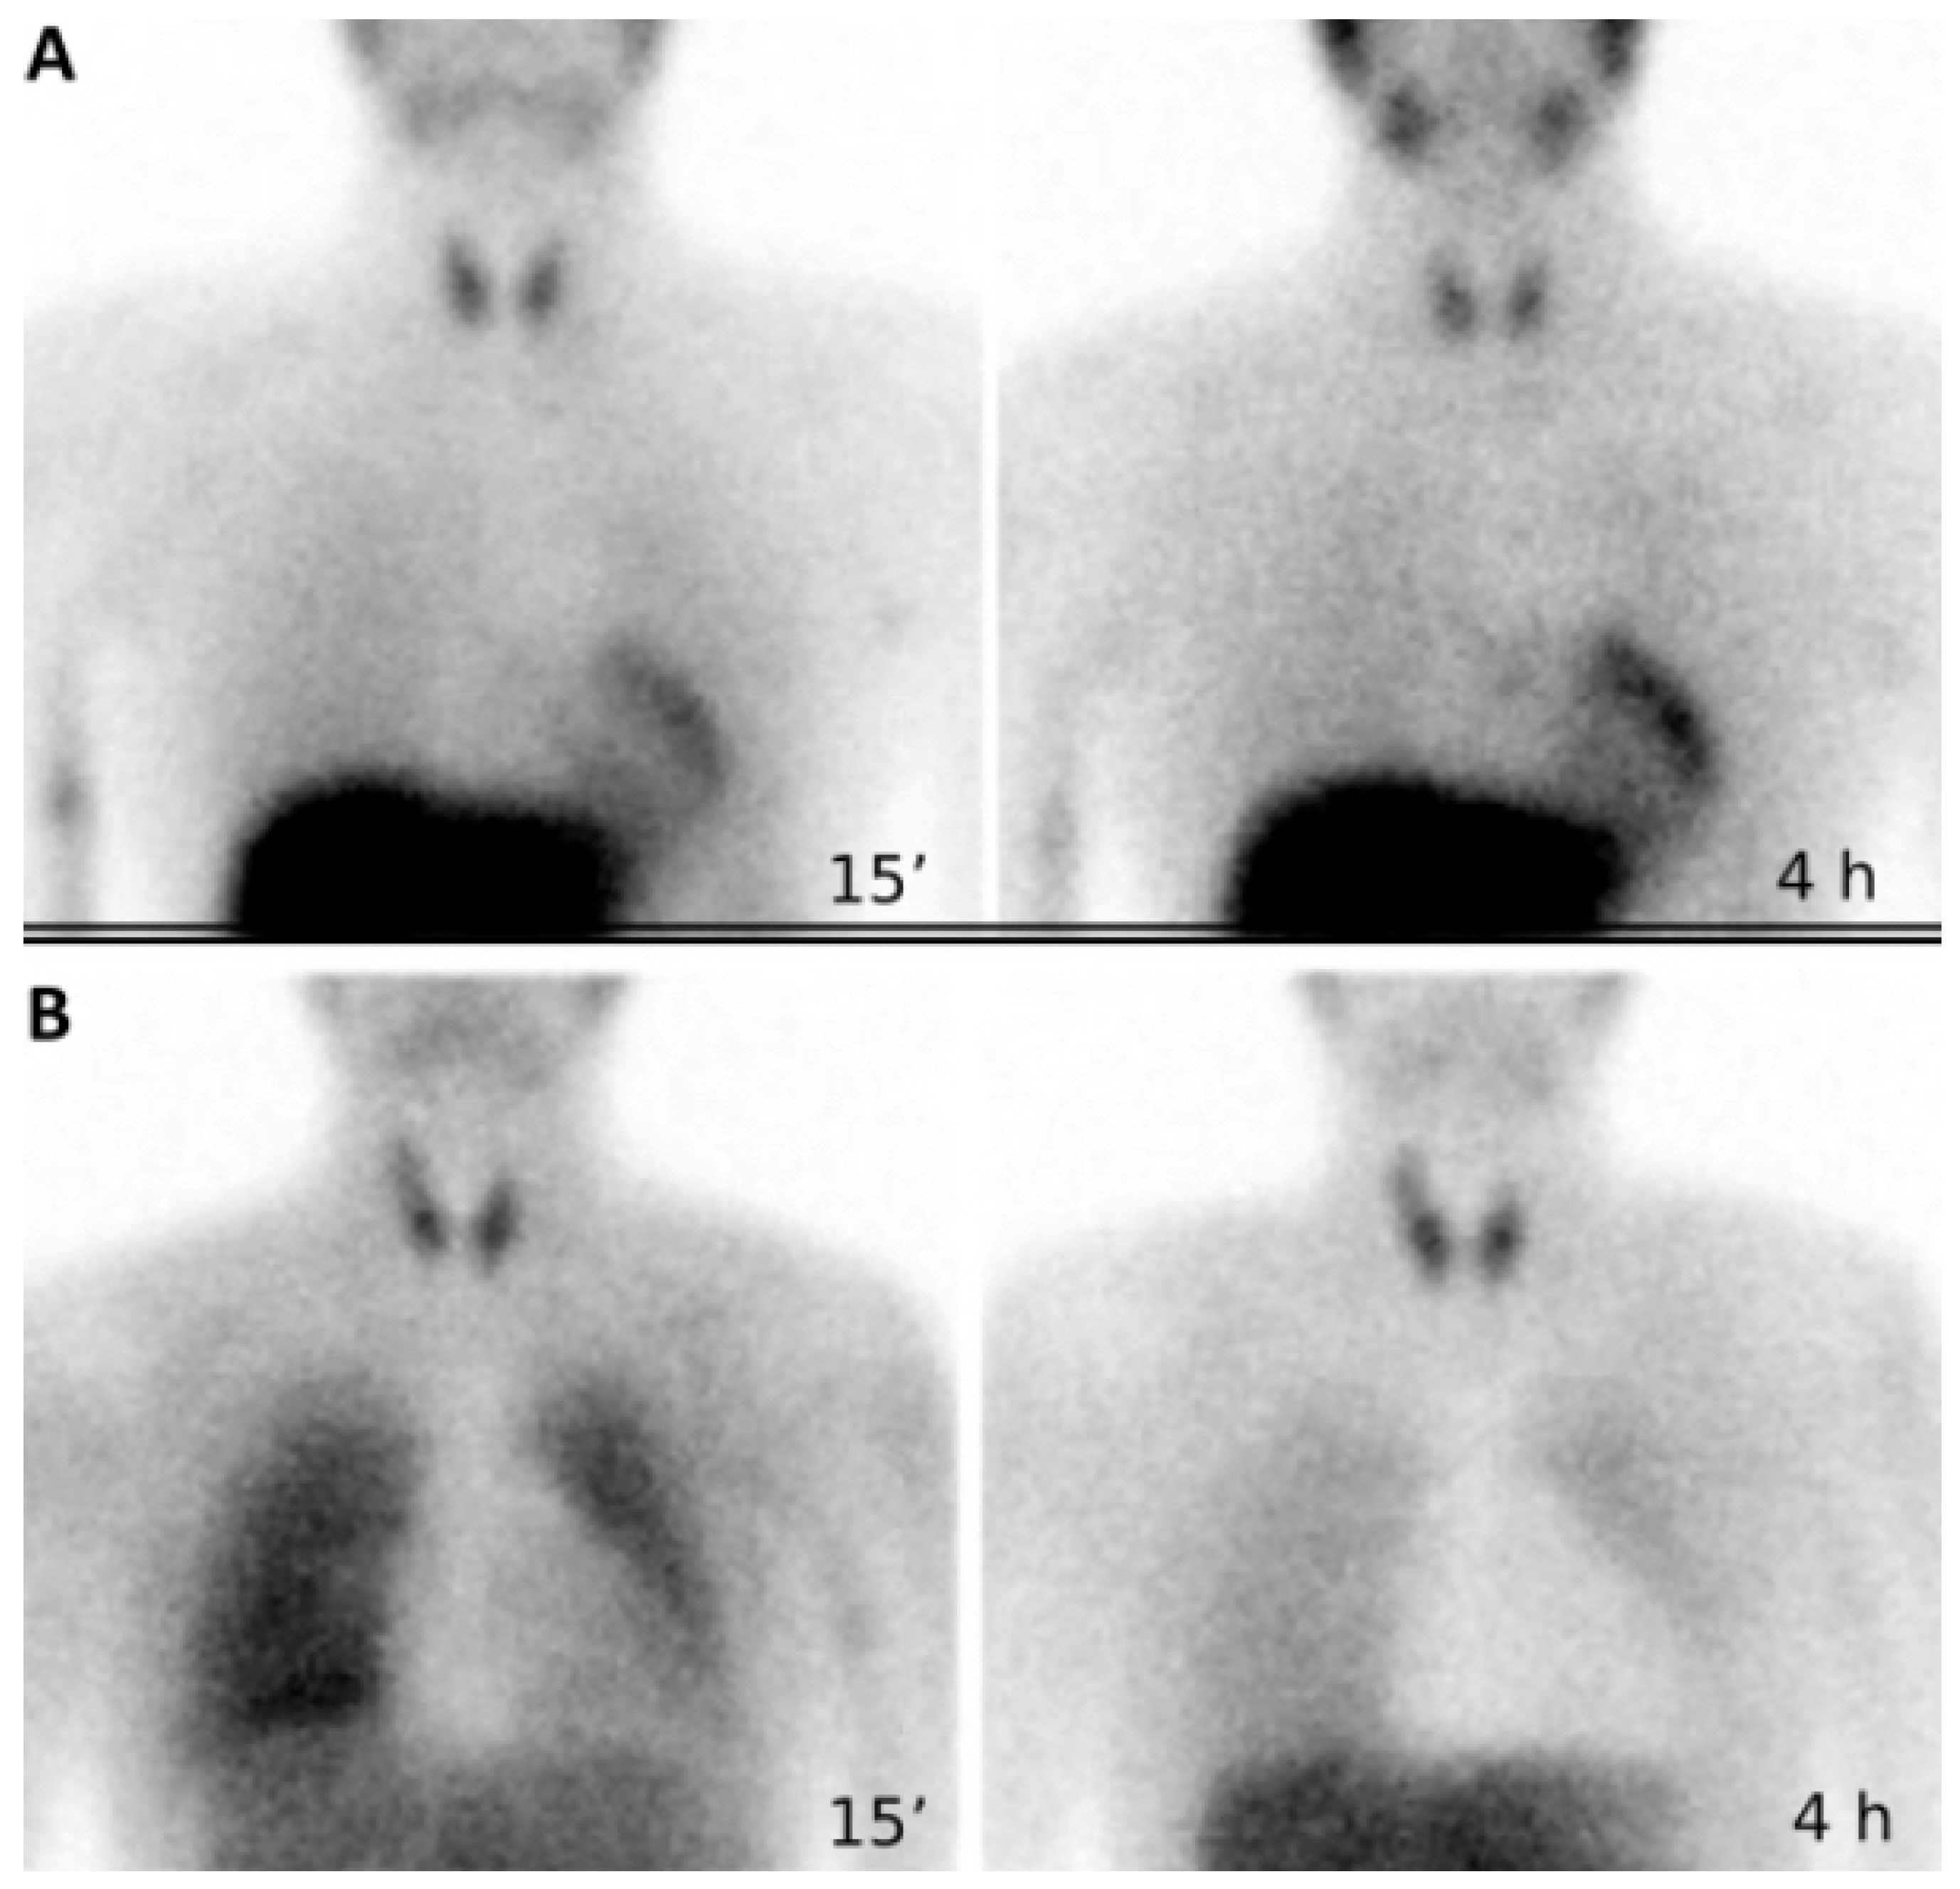

3.3. Cardiac Sympathetic Innervation

- With KD, probably due to coronary arteries stenosis [68].

- Zhao, C.; Shuke, N.; Yamamoto, W.; Okizaki, A.; Sato, J.; Kajino, H.; Fujieda, K.; Aburano, T. Impaired Cardiac Sympathetic Nerve Function in Patients with Kawasaki Disease: Comparison with Myocardial Perfusion. Pediatr. Res. 2005, 57, 744–748. [Google Scholar] [CrossRef] [PubMed][Green Version]

- Ono, S.; Ohuchi, H.; Miyazaki, A.; Abe, T.; Kiso, K.; Yamada, O. Heterogeneity of Ventricular Sympathetic Nervous Activity is Associated with Clinically Relevant Ventricular Arrhythmia in Postoperative Patients with Tetralogy of Fallot. Pediatr. Cardiol. 2015, 36, 1515–1522. [Google Scholar] [CrossRef]

- Kondo, C.; Nakazawa, M.; Momma, K.; Kusakabe, K. Sympathetic Denervation and Reinnervation After Arterial Switch Operation for Complete Transposition. Circulation 1998, 97, 2414–2419. [Google Scholar] [CrossRef] [PubMed]